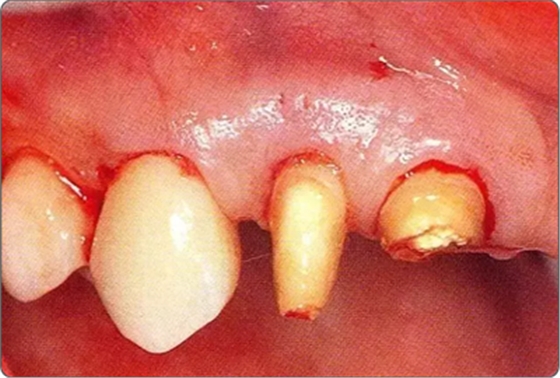

圖10-7 緊密貼合根面讓牙齦復(fù)位的狀態(tài)

圖10-8 上頜腭側(cè)處縫合的狀態(tài)。為獲得一次性創(chuàng)傷治愈進行了緊密縫合